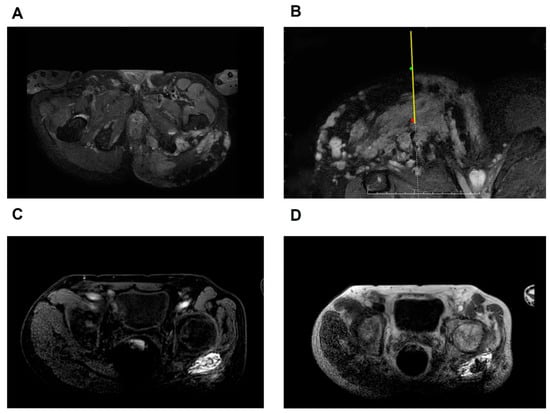

Objectives: Venous malformations (VMs) that infiltrate the muscular layer, involve or are closely adjacent to critical nerves or vessels, or are located deep within or very close to major organs in the thoracic or abdominal cavities are challenging to access during sclerotherapy, which [...] Read more.

Objectives: Venous malformations (VMs) that infiltrate the muscular layer, involve or are closely adjacent to critical nerves or vessels, or are located deep within or very close to major organs in the thoracic or abdominal cavities are challenging to access during sclerotherapy, which we defined as inaccessible VMs. This study proposed an integrated real-time stereotactic MRI-guided sclerotherapy with bleomycin-polidocanol foam (RSMS-BPF) for the treatment of inaccessible VMs, focusing on its clinical feasibility, efficacy, and safety. Methods: A retrospective study was conducted involving patients treated with RSMS-BPF between 2019 and 2021. During the sclerotherapy, the intraoperative magnetic resonance imaging (MRI) was combined with an optical navigation system to guide precise needle placement and track BPF, a foam sclerosant optimized for MRI visibility. Radiological response was assessed by lesion volume, while clinical improvement was evaluated through patients’ description of their symptoms. Rigorous follow-up and documentation of complications were conducted. Results: A total of 42 patients (mean age 23.6 ± 1.6 years; 18 males) were treated in 64 sclerotherapy sessions. The treatment achieved an overall response rate of 89.5%. Imaging analysis revealed an average lesion volume reduction of 59.6%. 57.9% of patients achieved good or excellent radiological responses. After a median follow-up of 12.25 months, 60.53% of patients reported complete or significant relief. Lesion depth did not affect treatment efficacy (p = 0.43). Minor complications included skin hyperpigmentation (5.3%, 2/38) and blisters (2.6%, 1/38), with no major complications observed. Conclusions: RSMS-BPF demonstrated satisfactory efficacy and safety in VMs treatment, particularly for inaccessible VM lesions. It enables authentic real-time dynamic tracking during sclerotherapy, achieving unparalleled precision targeting while minimizing procedural risks. These findings strongly support routine integration of RSMS-BPF as first-line therapy for complex vascular malformations with critical anatomical constraints. Full article